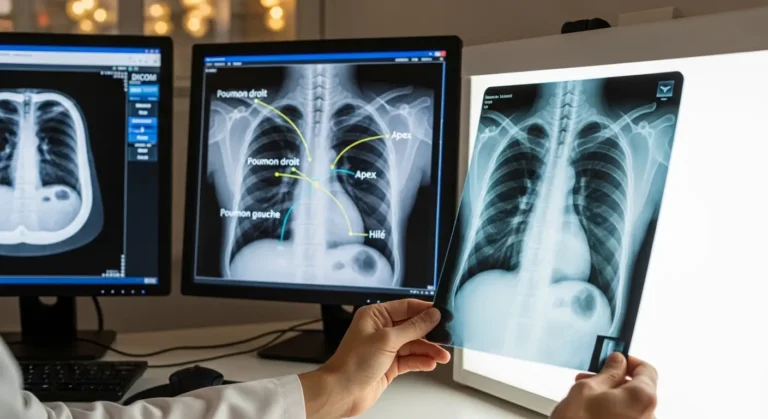

Si vous lisez votre compte rendu avant de voir votre médecin, voici un petit lexique :

| Terme médical | Ce que ça veut dire en clair |

|---|---|

| Opacité | Une zone plus blanche que la normale — peut indiquer une infection, un liquide, une tumeur |

| Condensation | Une zone du poumon qui n’est plus aérée — souvent signe de pneumonie |

| Épanchement pleural | Du liquide autour du poumon |

| Cardiomégalie | Le cœur est plus grand que la normale |

| Hyperclarté | Zone trop sombre — peut indiquer de l’air là où il ne devrait pas être |

| Réticulé / interstitiel | Un réseau de lignes anormales — souvent lié à des maladies chroniques |

La réponse des radiologues est claire : ne tirez aucune conclusion par vous-même. Une anomalie sur une radio pulmonaire peut avoir des dizaines d’explications différentes, allant du simple ganglion calcifié (cicatrice d’une ancienne infection bénigne) à quelque chose nécessitant un suivi.